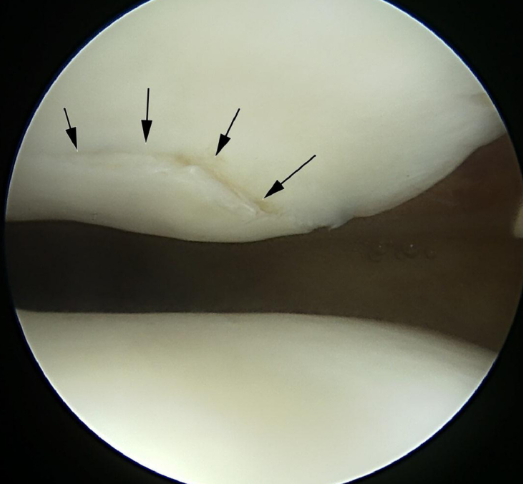

MRI(자기공명영상): 연골의 상태, 손상 정도, 주변 조직의 이상유무까지 정밀하게 확인할 수 있는 가장 유용한 검사입니다. 연골 조직의 부드러워짐, 두께 감소, 미세한 균열 등도 평가 가능합니다.

관절경: 진단이 어렵거나, 수술을 목적으로 할 때 시행되는 검사로, 관절 안을 직접 카메라로 보면서 연골의 변화 정도를 확실히 판단할 수 있습니다. 그러나 비침습적 진단법이 우선 시행됩니다.